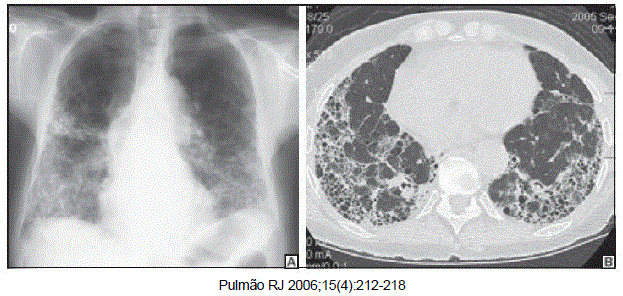

Mulher de 69 anos de idade, natural e procedente de São Paulo é dentista. Tabagista de 20 maços-ano, apresenta dispneia e tosse seca há 2 anos, sem outras queixas. No exame clínico apresenta saturação de oxigênio de 90% em ar ambiente e estertores em velcro bilaterais, sendo o restante do exame clínico normal. A radiografia e tomografia de tórax estão a seguir. A espirometria mostra VEF1 e CVF diminuídos com relação VEF1/CVF preservada.

Qual é a principal hipótese diagnóstica?